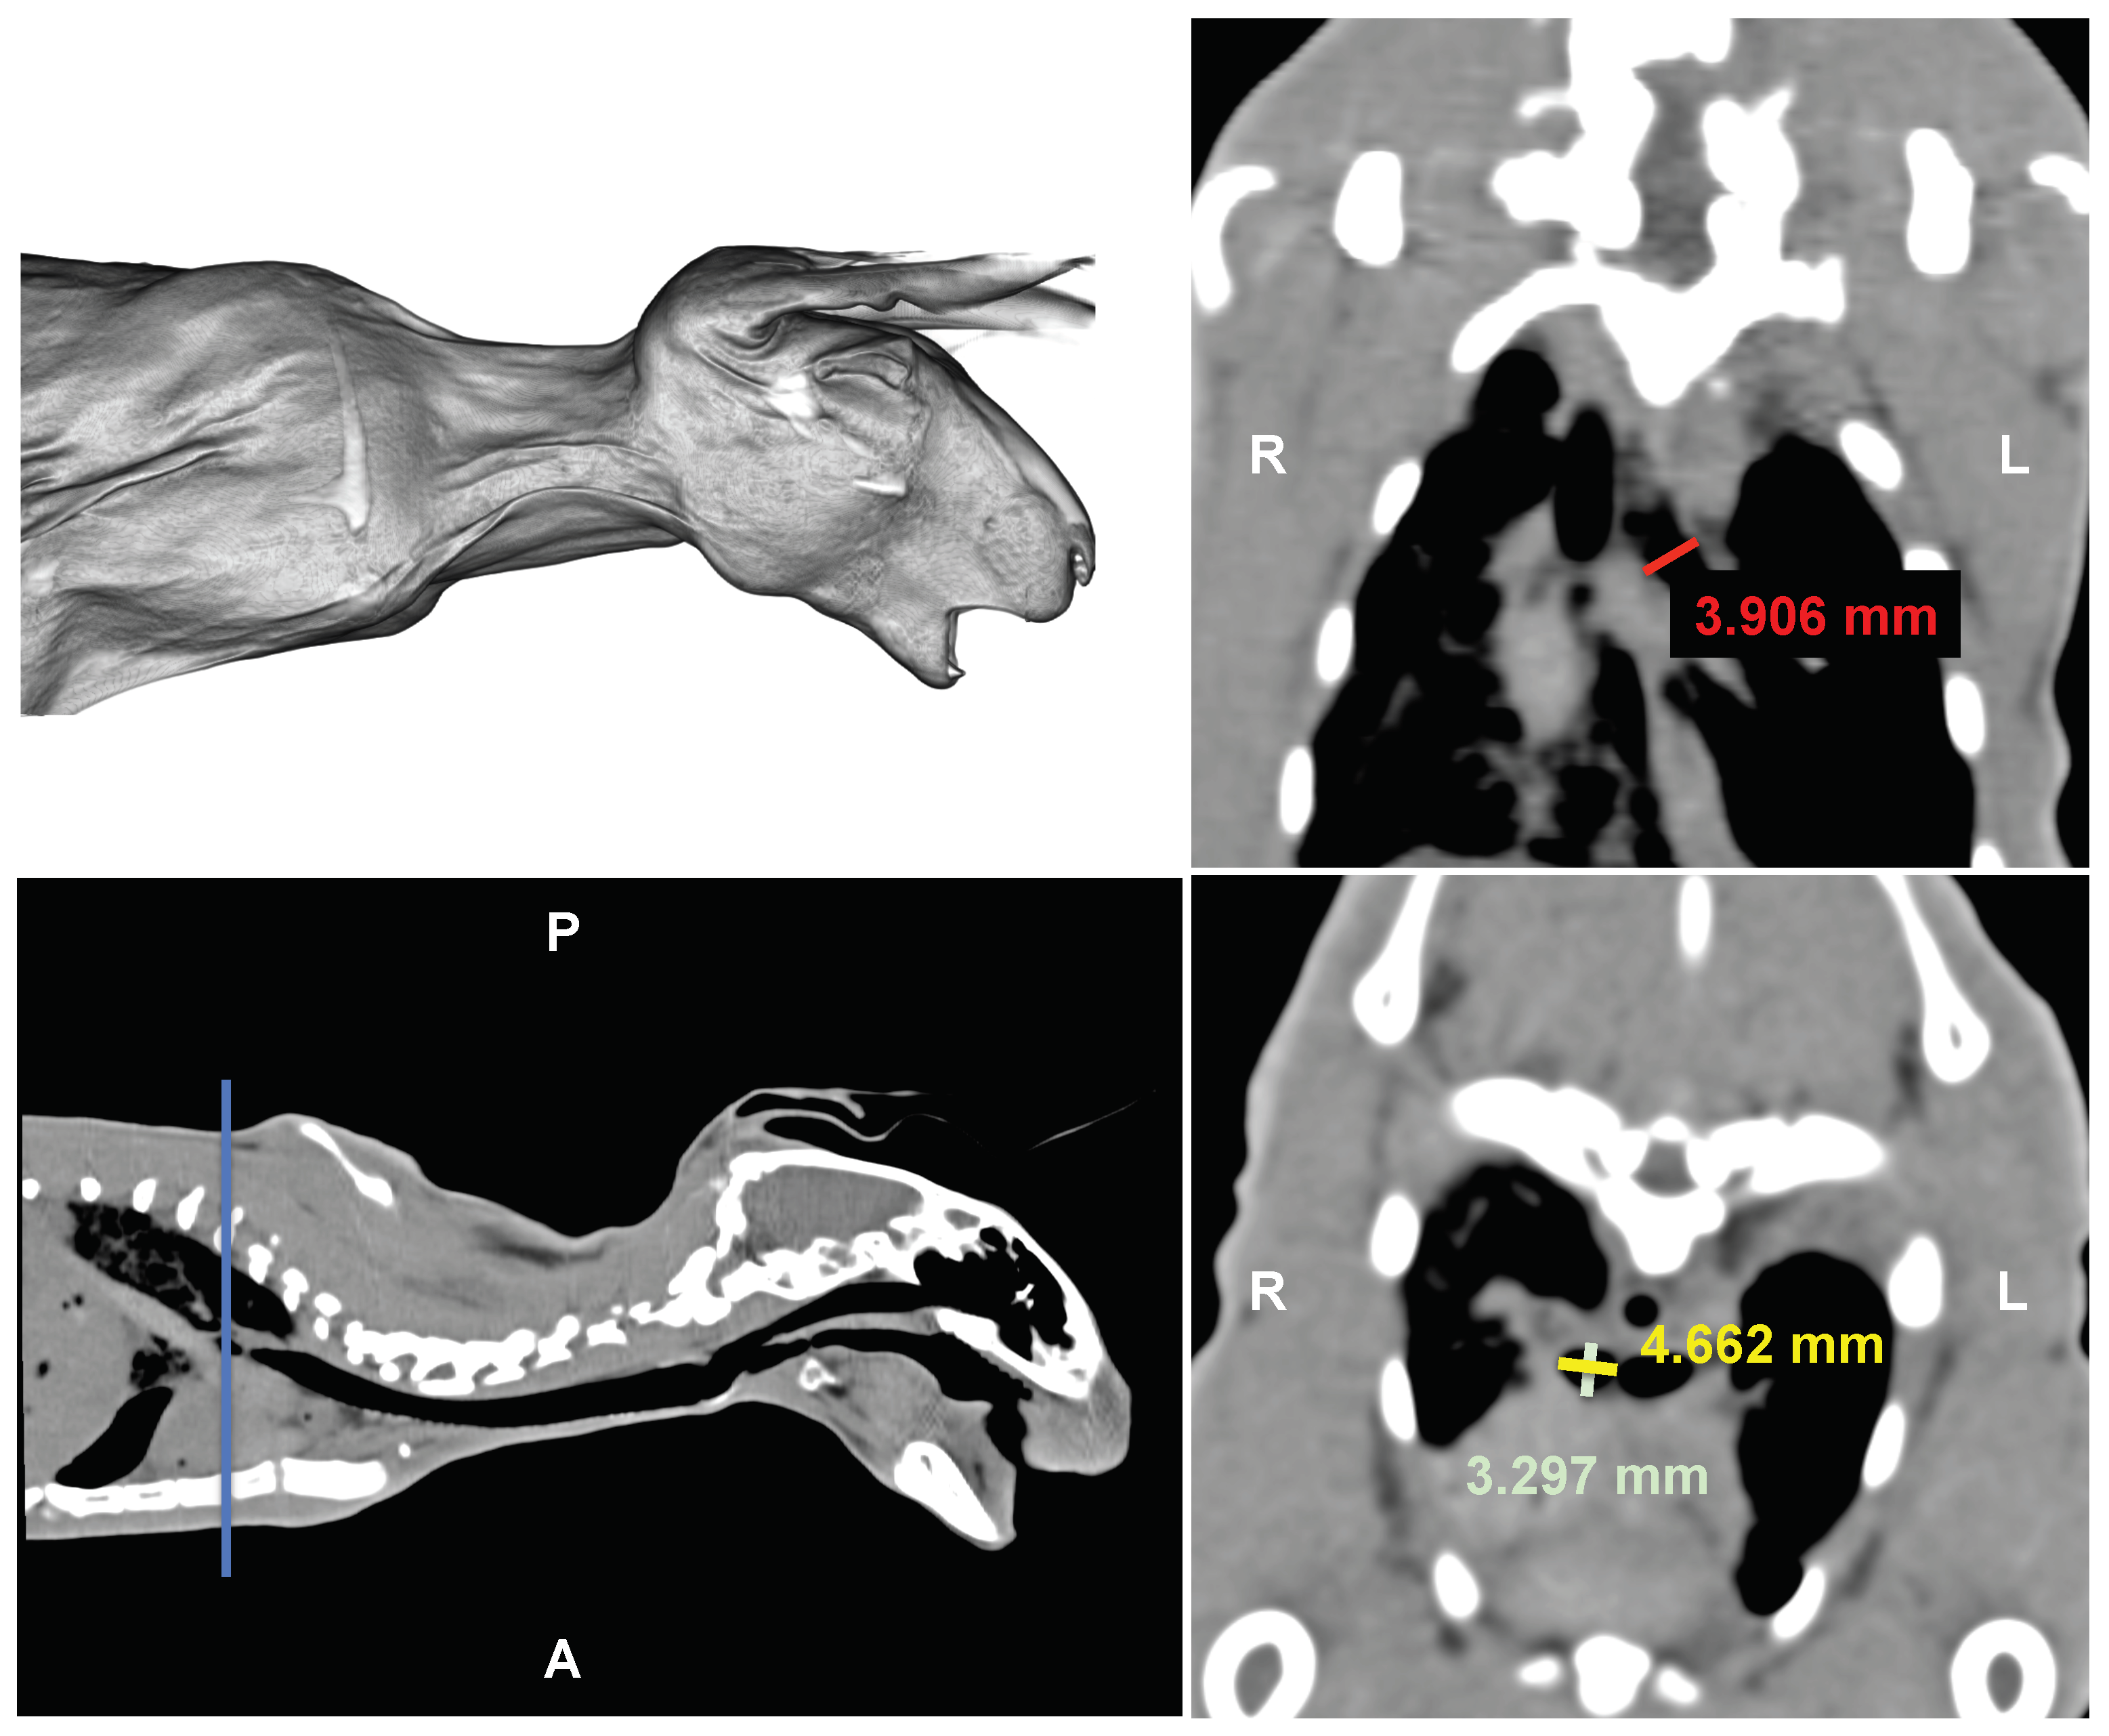

Figure 4.

Ex vivo study: Computerized tomography images of a cadaveric rabbit head, neck and thorax. Upper left: 3D rendering. Upper right: Dorsal multiplanar reconstruction. Lower left: sagittal scan. Lower right: transversal scan. Red line: right bronchial length. Yellow and green lines: left bronchial diameters. Blue line: anatomical locator. L = left, R = right, A = anterior, P = posterior.

The crimping head is modeled as a rigid cylinder, with its internal diameter corresponding to the external diameter of the stent (see Figure 3). Radial compression simulation involves applying a radial displacement as a boundary condition. The compression is driven by the cylinder, causing the stent diameter to decrease from its initial value of 5 mm during crimping, to 3 mm during compression and then returning to 5 mm, as shown in Figure 3. This corresponds to a radial deformation of . The initial diameter was selected based on the stent’s testing in rabbits during an ex vivo pilot study (refer to Figure 4). The rationale for using rabbit airway dimensions in the computational study is to assess the initial dimensions of the stents that will be introduced later in the in vivo study in rabbits. This approach aims to evaluate the consequences of the interaction between biological tissue and the medical device. While the in vivo study is being pursued in a parallel work, the objective of the ex vivo study is solely to determine the feasibility of introducing the new stent designs into the rabbit airway, specifically finding the adequate inner radius. As an example, a computerized tomography (CT) scan from a rabbit cadaver is shown in Figure 4. The stents required adaptation to fit the dimensions of the rabbit bronchi, which were measured with the open-source software HorosTM (GNU Lesser General Public License, Version 3 (LGPL-3.0)) revealing a diameter of , and mm for the left and the right stem respectively in the absence of airway lesions (see Figure 4). Measurements were obtained separately for the left and right bronchi from the dorsal and transversal thorax scan (see Figure 4 right upper and lower panel). The additional measurements obtained from other rabbits with similar body weights revealed similar measures, in all cases less than 5 mm, which was finally fixed as initial dimension of the device. The interaction between the inner surface of the crimping head and the external surface of the wires was assumed to be frictionless. To prevent rigid body movement, a remote displacement of a node in the middle of each stent was restrained. Finally, the radial force of the stent was computed from the reaction force acting on the cylinder. The simulations were performed using Ansys (release 2020 R2) on an Hp Z2 G4 Workstation equipped with 8 Cores Intel i9, 3.6 GHz and 16 GB RAM.